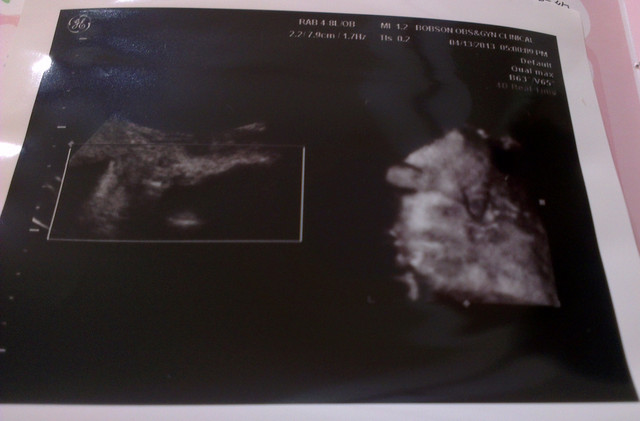

看看一開始產檢醫生幫我拍的照片

章魚妹妹在打呵欠啊

嘴巴張這麼大